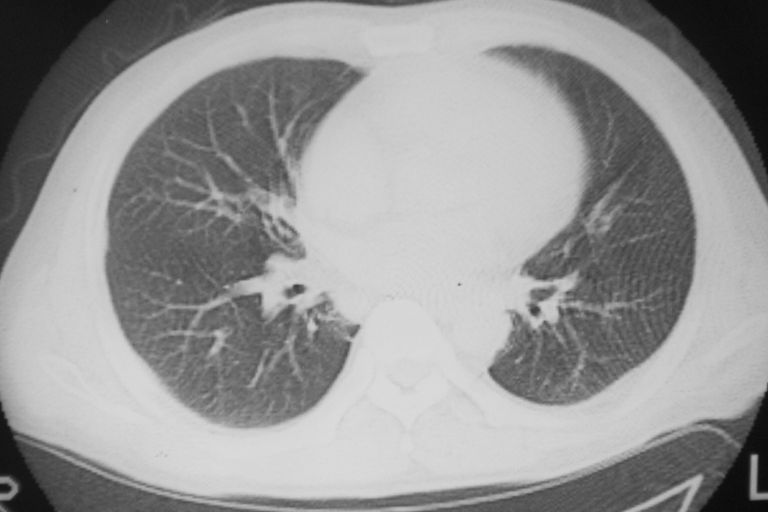

患者 男 50岁 无痛性咯血3天,无其他不适.

左下肺结节状软组织密度影,边缘有毛刺,考虑周围型肺癌。

1 左肺下叶基底段见两结节软组织密度灶, 肺窗边缘见有毛刺征像, 不能排除占位. 2 建议结合临床治疗一周后ct随访在看其结果.

临近胸膜增厚,病变周围肺不清,稍有分叶。结节密度略高,肺、纵隔窗差异不大,肺癌待排。前方还有一个